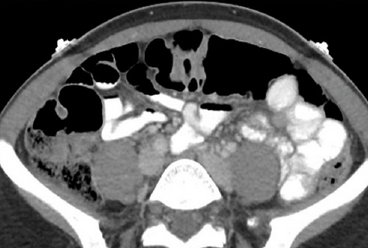

Контрастное усиление при обследовании легких проводят тогда, когда необходимо усилить четкость изображения в таких ситуациях:

- для выявления гнойных очагов с полостями распада и участками некроза,

Очаг некроза в легком: снимок без контраста слева и с контрастом справа

- при дифференциальной диагностики доброкачественных и злокачественных опухолей,

- для уточнения локализации патологических очагов, их распространенности и степени поражения соседних тканей.

Снимок легкого до введения контраста (слева) и после (справа — выявлены патологические очаги)